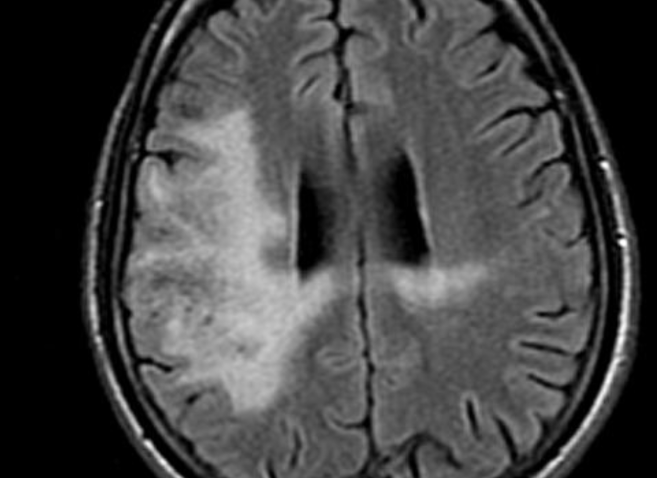

Lecoencéphalopathie Multifocale Progressive (LEMP / PML)

- JC Virus (réactivation)

- Patients immunodéprimés ++ (HIV, transplantés)

- SEP sous Tysabri (Natalizumab) = Rares

- Démyélinisation asymétrique avec atteinte des fibres en U

- Les lesions partent des fibres en U et s’étendent en profondeur

- La prise de contraste est en périphérie (front actif)

- Pas d’effet de masse (pas un processus infiltratif)

- Diagnostic final PCR voir biopsie cérébrale

- Mauvais pronostic (péjoration progressive → décès)

- Le Front infllammatoire peut se “reveiller” quand le patient regagne une immunité et mimer une progression alors que c’est la réponse immunitaire = IRIS (Immune reconstitution inflammatory syndrome)